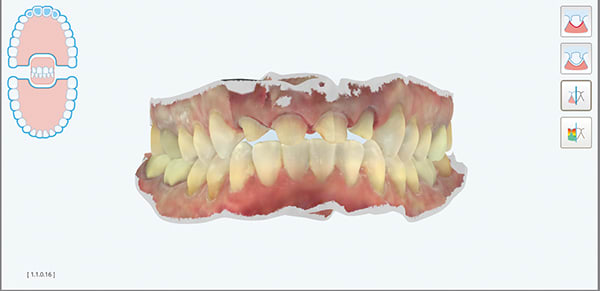

A female patient aged 57 years presented with altered passive eruption of the maxillary anterior teeth, which was diagnosed as a secondary condition to tooth erosion resulting from long-standing gastroesophageal reflux disease (GERD). Clear aligner therapy was initiated to level and align the occlusion and intrude the maxillary anterior teeth back to their original gingival position. After 18 months of poor patient compliance, improvement in tooth position was minimal and the amount of clinical overjet that was desired was not achieved. This limited the restorative armamentarium, and a decision was made to proceed with monolithic zirconia-oxide restorations. Following teeth preparation and tissue retraction, the case was impressed using an intraoral scanner (iTero® Element 2, Align Technology, Inc., itero.com). The final restorations were made of zirconium dioxide with a feldspar veneering ceramic shade 1M1 as the pressed layer on porcelain on the facials. The outcome of the case met the patient's primary concerns, achieving the lengthening and lightening of the anterior teeth that she desired. Because of the patient's continued challenges with GERD, however, she reported having difficulty with compliance related to the clear aligner therapy and whitening protocols, precluding a more ideal result. Nonetheless, the patient was pleased with her new smile and the clinician, given the challenging circumstances, was satisfied with the clinical results of the final restorations.

A key component of the zirconia-based treatment for this case was the use of an intraoral scanner for digital impressions, which allowed for clear marginal visualization, time efficiency, and a simplified impression process.